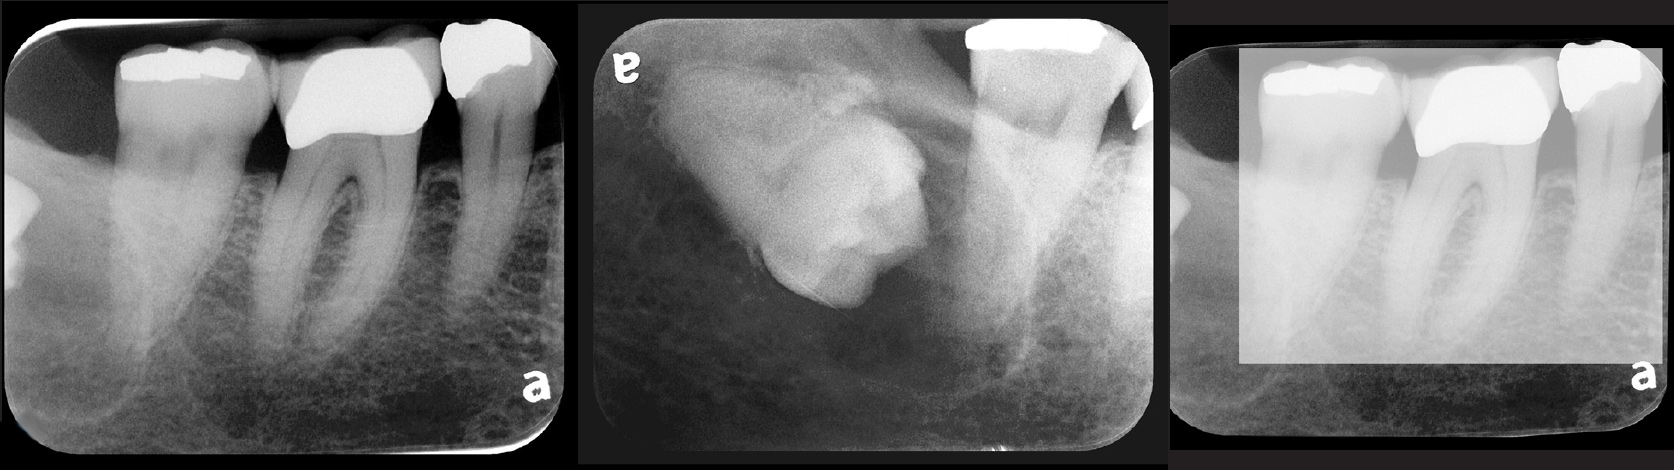

Fig 5. Bilateral concerns for this patient are evident on these PSP

radiographs. Tooth No. 17 may exhibit pathology distal to the root. In

addition, extreme length of root of tooth No. 32 through the entire height

of the body of the mandible is cause for concern if extractions of Nos.

17 and 32 are planned. Three-dimensional CBCT study and alerts to

the patient as to the potential surgical complications on extractions are

required in this instance. There is no benefit to panoramic radiography

in this case.

Figure 5

Fig 6. PA radiograph showing 90-degree dilacerations of

mesial and distal roots of tooth No. 32 and intersection of mandibular

canal with these roots. Extraction of tooth No. 32 requires 3D study, and

patient was advised as to this necessity.

Figure 6

Fig 7. Presence on maxillary

anterior PSP PA radiograph of impacted canine No. 11.

Figure 7

Fig 8. PSP

PA radiograph demonstrates view of impacted supernumerary tooth

between the roots of tooth Nos. 27 and 28.

Figure 8